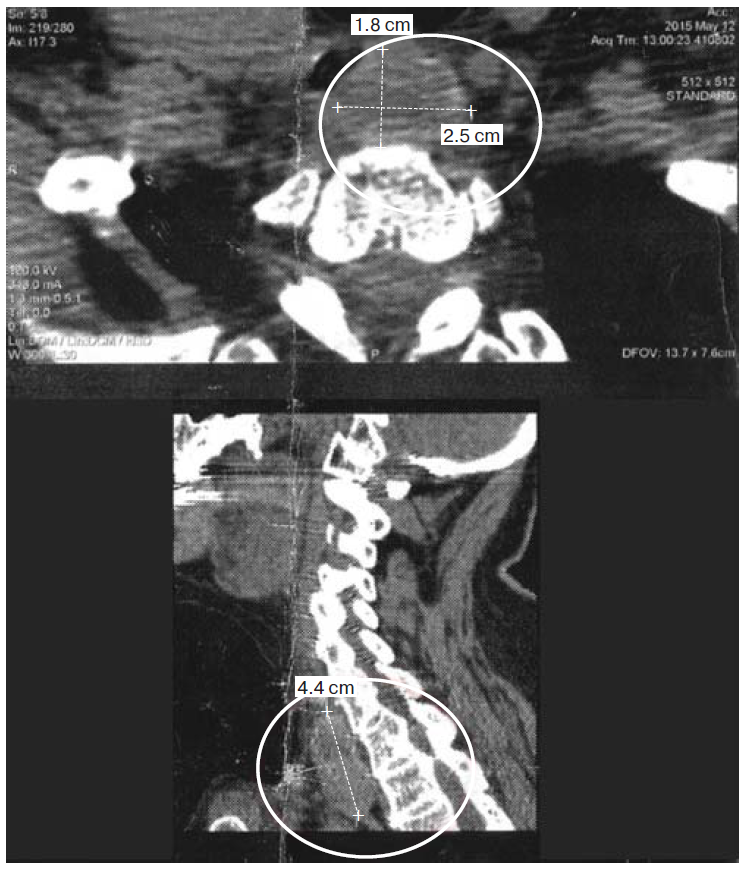

4. Fig. 3. Magnetic resonance tomogram of soft Neck tissue and computer tomogram of organs thoracic cavity. | |